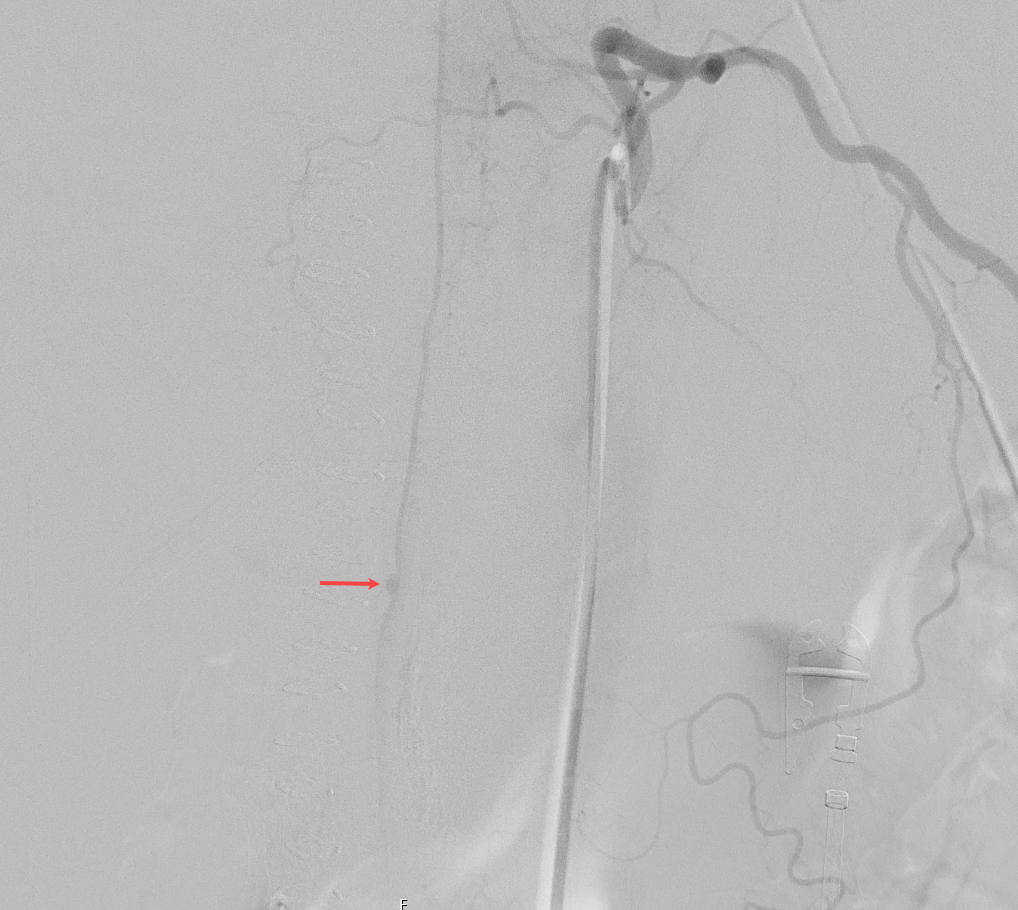

Arteria spinalis anterior Aneurysma Angiographie

Spinale DSA eines Patienten mit einem Aneurysma der Arteria spinalis anterior.